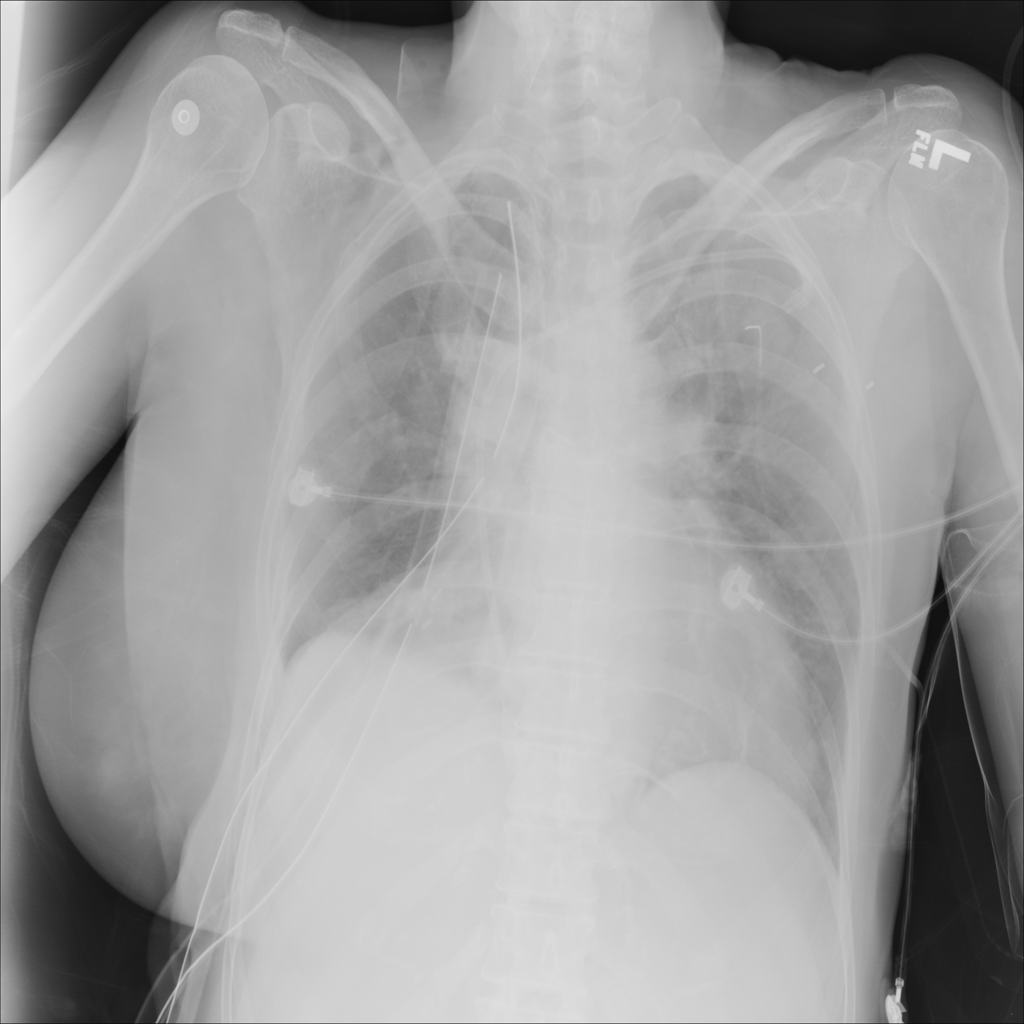

PAT-0E82 · IMG-000Emphysema

PAT-0E82 · IMG-000

AP